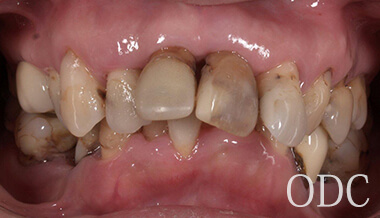

術 前

術前

初診時87歳、男性。上顎は歯周病により残存歯を長期的に機能させることが困難と判断し、全て抜歯。出来る限り早期の咬合機能の回復と審美性の実現が求められ、上顎は「4本のインプラントで失った全ての歯を固定し、手術当日から噛む機能を回復させることが可能」なオールオン4という術式を選択。オールオン4は「治療期間」「経済性」「審美性」「外科的侵襲」などのあらゆる負担を軽減した全く新しいコンセプトの画期的なインプラント治療です。 下顎の欠損部位に対しても、術前の診査診断をしっかり行い合計5本のインプラントを埋入しました。